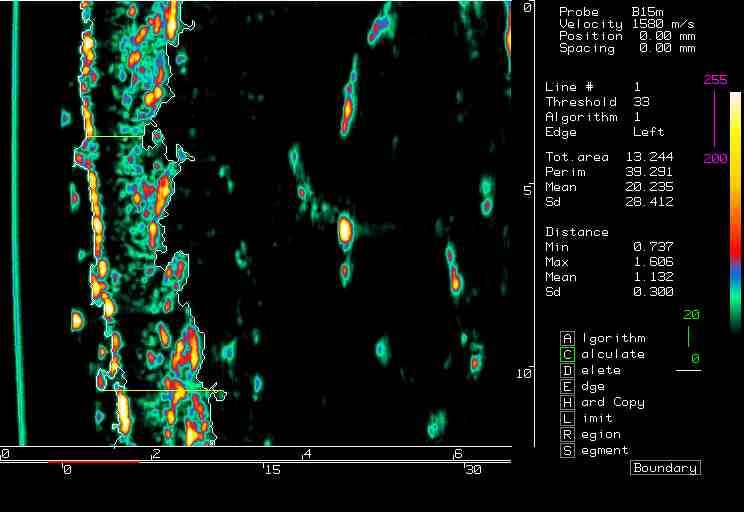

| Shaving reactions |  Cheek, prior to shaving |

Cheek, 0 min post shaving |

Cheek, 90 min post shaving |